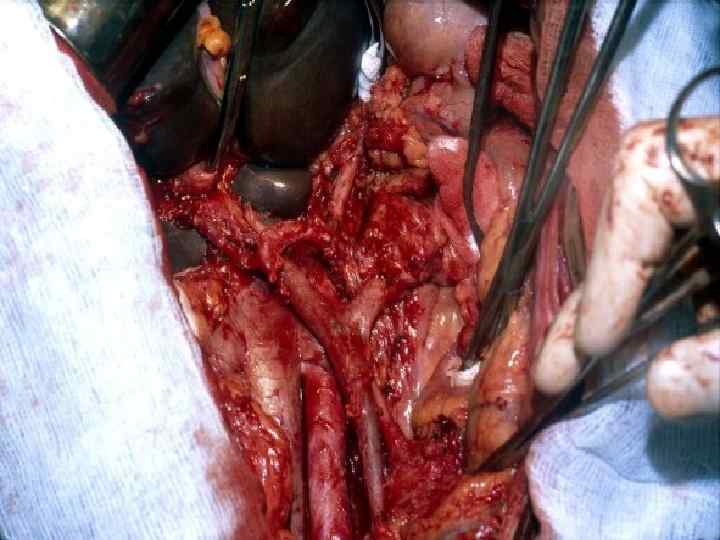

Этапы стандартной ГПДР • • • 1. Мобилизация 12 -перстной кишки 2. Выделение трубчатых структур гепато-дуоденальной связки 3. Выделение верхней брыжеечной вены 4. Мобилизация и отсечение дистальной части холедоха 5. Мобилизация и пересечение начальной части тощей кишки 6. Пересечение гепатикохоледоха после мобилизации желчного пузыря • 7. Пересечение поджелудочной железы по перешейку • 8. Пересечение связок крючковидного отростка, удаление комплекса • 9. Реконструктивный этап

Резекция чревного ствола и общей печёночной артерии при выполнении ДСРПЖ Вид резекции Циркулярная резекция чревного ствола Всего Число больных с пластикой 4 без пластики 11 15